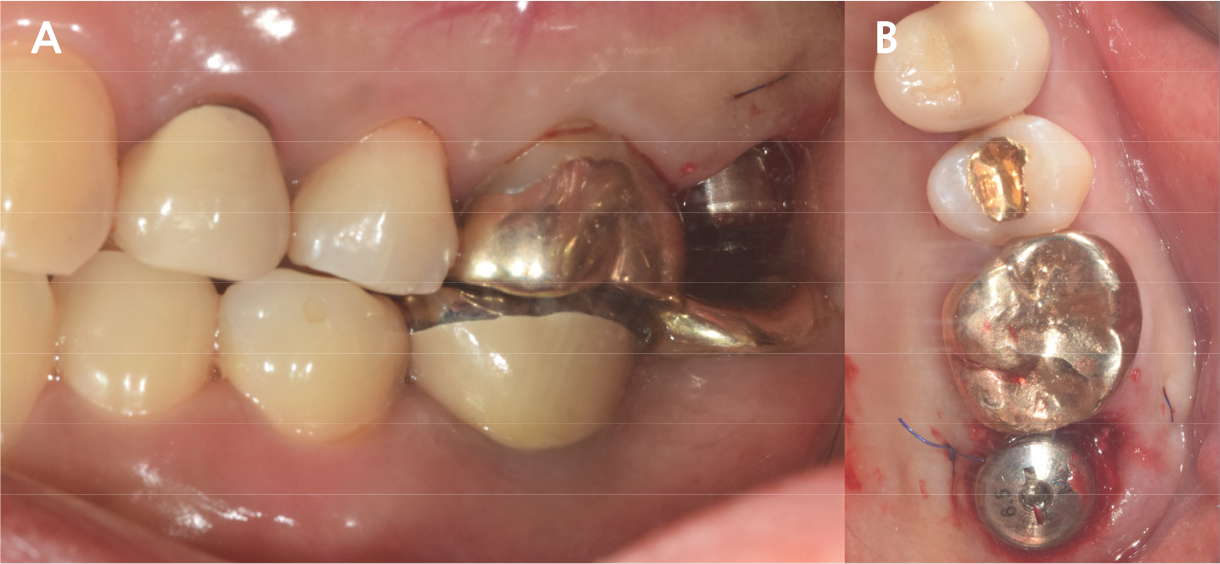

An implant with 5.0 mm diameter and 8.0 mm length (Superline; Dentium, Seoul, Korea) was placed with 0.5 cc of eproteinized bovine bone mineral (DBBM; Bio-Oss®, Geistlich, Wolhusen, Switzerland) by sinus elevation. The implant stability quotient (ISQ) after placement was 64 continually and the healing abutment was placed (6.5 mm diameter, height M size) (Fig. 4A, 4B). Postoperative antibiotics (Sultamox Tab. 500 mg; Alvogen, Seoul, Korea) and analgesics (Somalgen Tab. 370 mg; Alvogen), digestive agent (Beszyme Tab. 470 mg; Dong-A ST, Seoul, Korea) were prescribed for 5 days (30 min after meal). Gargle agent (G.U.M® Dental Rinse S; Sunstar, Osaka, Japan) with no toothbrushing was prescribed to drain and protect the operation area for 2 weeks. Postoperative cone-beam computed tomography (CBCT) showed a dome-shaped elevated membrane with a heterogeneous bone graft surrounding dental implants (Figs. 5 and 6). After 14 days, favorable healing gingiva was confirmed with the stitch-out process (Fig. 7).

After 4 months of the first surgery, the ISQ value was 71, showing favorable stability, the prosthesis was placed consecutively, and healing progress was observed (Fig. 8A, 8B). After 5 months, the final prosthesis was completed (Fig. 9A, 9B). Supported treatment was initiated and radiographs were taken after 6 months (Figs. 10, 11, 12). In the radiograph analysis, the alveolar bone surrounding the dental implant was stable, with ossified bone verified. In a 6-month interval, the supported treatment was conducted in April 2022, showing no signs of peri-implant gingivitis or bone resorption (Figs. 13 and 14).